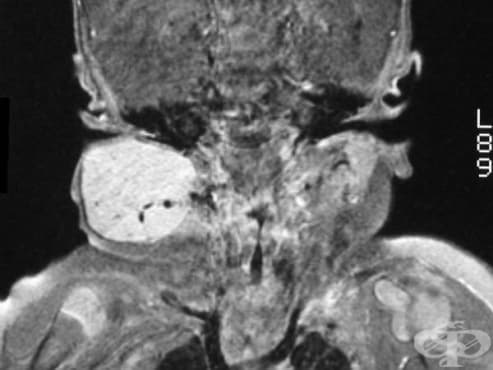

Образното изследване на избор при определяне на локализацията и разпространението на кожните и екстракутанните хемангиоми е ядрено-магнитен резонанс с или без използване на контрастно вещество гадолиний. ЯМР също помага за при отдиференцирането на хемангиомите от други съдови лезии.

Детски хемангиоми Детски хемангиоми Детски хемангиоми Детски хемангиоми Детски хемангиоми Нарушено зрение от хемангиома Улцерация на хемангиома Повърхностен хемангиом Дълбок хемангиом Смесен хемангиом Хистопатология на пролиферативен инфантилен хемантиом Изследване - оцветяване на глюкозен транспортер 1 (GLUT-1) ЯМР на детски хемангиом Хемангиом Белег от хемангиом Хемангиом